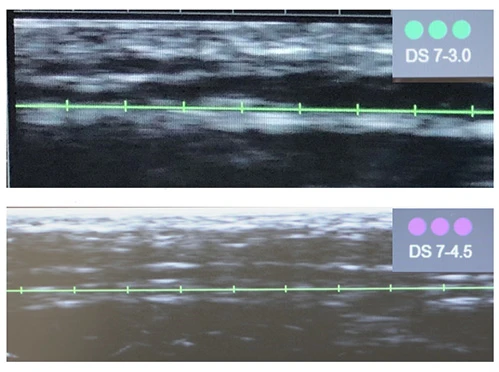

Диагностическая визуализация

Диагностическая визуализация. Протокол лечения: DS 7–4,5 60 линий, DS 7–3,0 600 линий; DS 10–1,5 60 линий. Суммарно все лицо, включая субментальную зону: 720 линий.